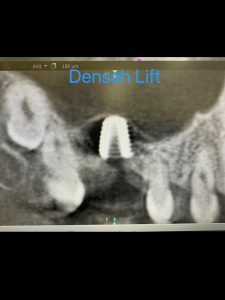

昼間からは、危ない動脈近接のソケットリフト

バッチリ👍避けるコツがある💪

5ミリで骨折、自己採血2本メンブレン挿入

計測値バッチリ75後半👍👌